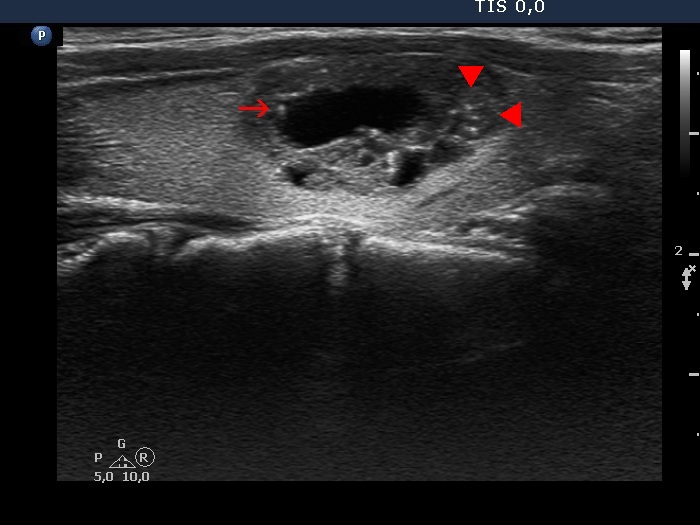

Benign cystic degeneration (cytological diagnosis) - case 1669

The lesion contains various figures: there is a comet-tail artifact marked with arrow, there are optical artifacts caused by posterior enhancement in the back wall of the cysts. However, the categorization of hyperechogenic granules (arrowheads) in the solid part of the lesion is obscure; these might be punctate echogenic foci (microcalcifications).

Papillary carcinoma (histological diagnosis) - case 853